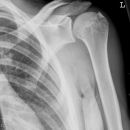

Kalkdepotinsertion Suprascapularis